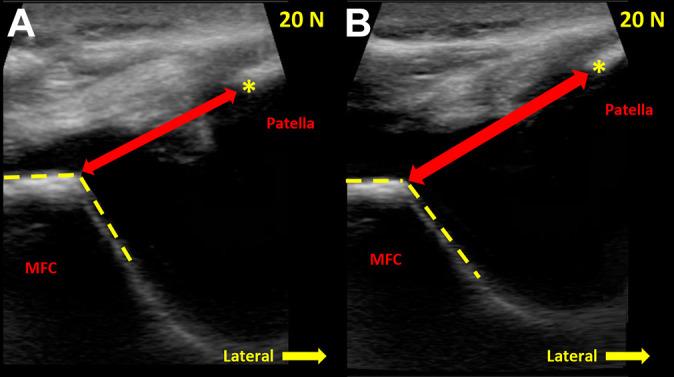

In 10 cadaveric knees, the medial patellofemoral distance was measured to quantify patellar position from 0° to 40° of knee flexion at 10° increments. Knees were evaluated at each flexion angle under unloaded conditions and with 20 N of laterally directed force on the patella to mimic the glide test. Patellar position measurements were made on ultrasound images obtained before and after MPFC transection and compared for significant differences. To determine the ability of medial patellofemoral measurements to differentiate between MPFC-intact and MPFC-deficient states, area under the receiver operating characteristic (ROC) curve analysis and the Delong test were used. The optimal cutoff value to distinguish between the deficient and intact states was determined using the Youden statistic.

A significant increase in medial patellofemoral distance was observed in the MPFC-deficient state as compared with the intact state at all flexion angles ( = .005 to < .001). When compared with the intact state, MPFC deficiency increased medial patellofemoral distance by 32.8% (6 mm) at 20° of knee flexion under 20-N load. Based on ROC analysis and the statistic, the optimal threshold for identifying MPFC injury was 19.2 mm of medial patellofemoral distance at 20° of flexion under dynamic loading conditions (area under the ROC curve = 0.93, sensitivity = 77.8%, specificity = 100%, accuracy = 88.9%).

对10具尸体膝关节,以10°的增量测量髌股内侧距离,以量化膝关节从0°到40°屈曲时的髌骨位置。在每个屈曲角度下,分别在无负荷条件下以及对髌骨施加20 N侧向力以模拟滑动试验的情况下对膝关节进行评估。在MPFC横断前后获取的超声图像上进行髌骨位置测量,并比较有无显著差异。为了确定髌股内侧测量区分MPFC完整和MPFC缺陷状态的能力,使用了受试者操作特征(ROC)曲线分析下的面积和德龙检验。使用约登统计量确定区分缺陷和完整状态的最佳临界值。

与完整状态相比,在所有屈曲角度下,MPFC缺陷状态下的髌股内侧距离均显著增加(P = 0.005至P < 0.001)。与完整状态相比,在20 N负荷下膝关节屈曲20°时,MPFC缺陷使髌股内侧距离增加了32.8%(6 mm)。基于ROC分析和约登统计量,在动态加载条件下,屈曲20°时识别MPFC损伤的最佳阈值是髌股内侧距离为19.2 mm(ROC曲线下面积 = 0.93,灵敏度 = 77.8%,特异性 = 10